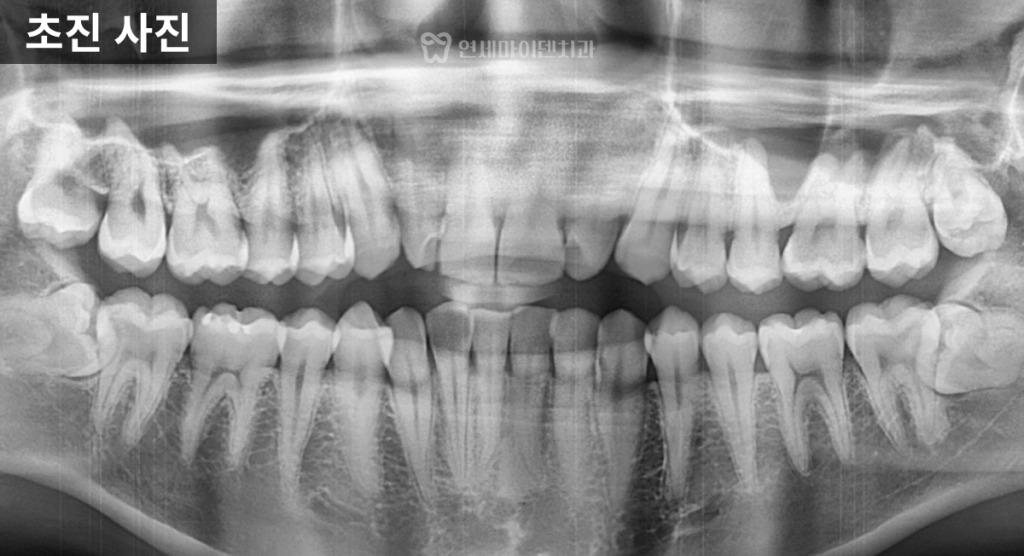

특히 두 번째 앞니는

크기가 작은 왜소치 형태를 띠고 있었고,

사랑니는 매복된 상태로

발치가 필요한 상황이었습니다.

다행히 전반적인 치근 상태는

양호한 편이었습니다.

방사선 사진 분석 결과,

위턱보다 아래턱이 더 발달한

3급 부정교합,

흔히 주걱턱이라고 불리는 상태였습니다.